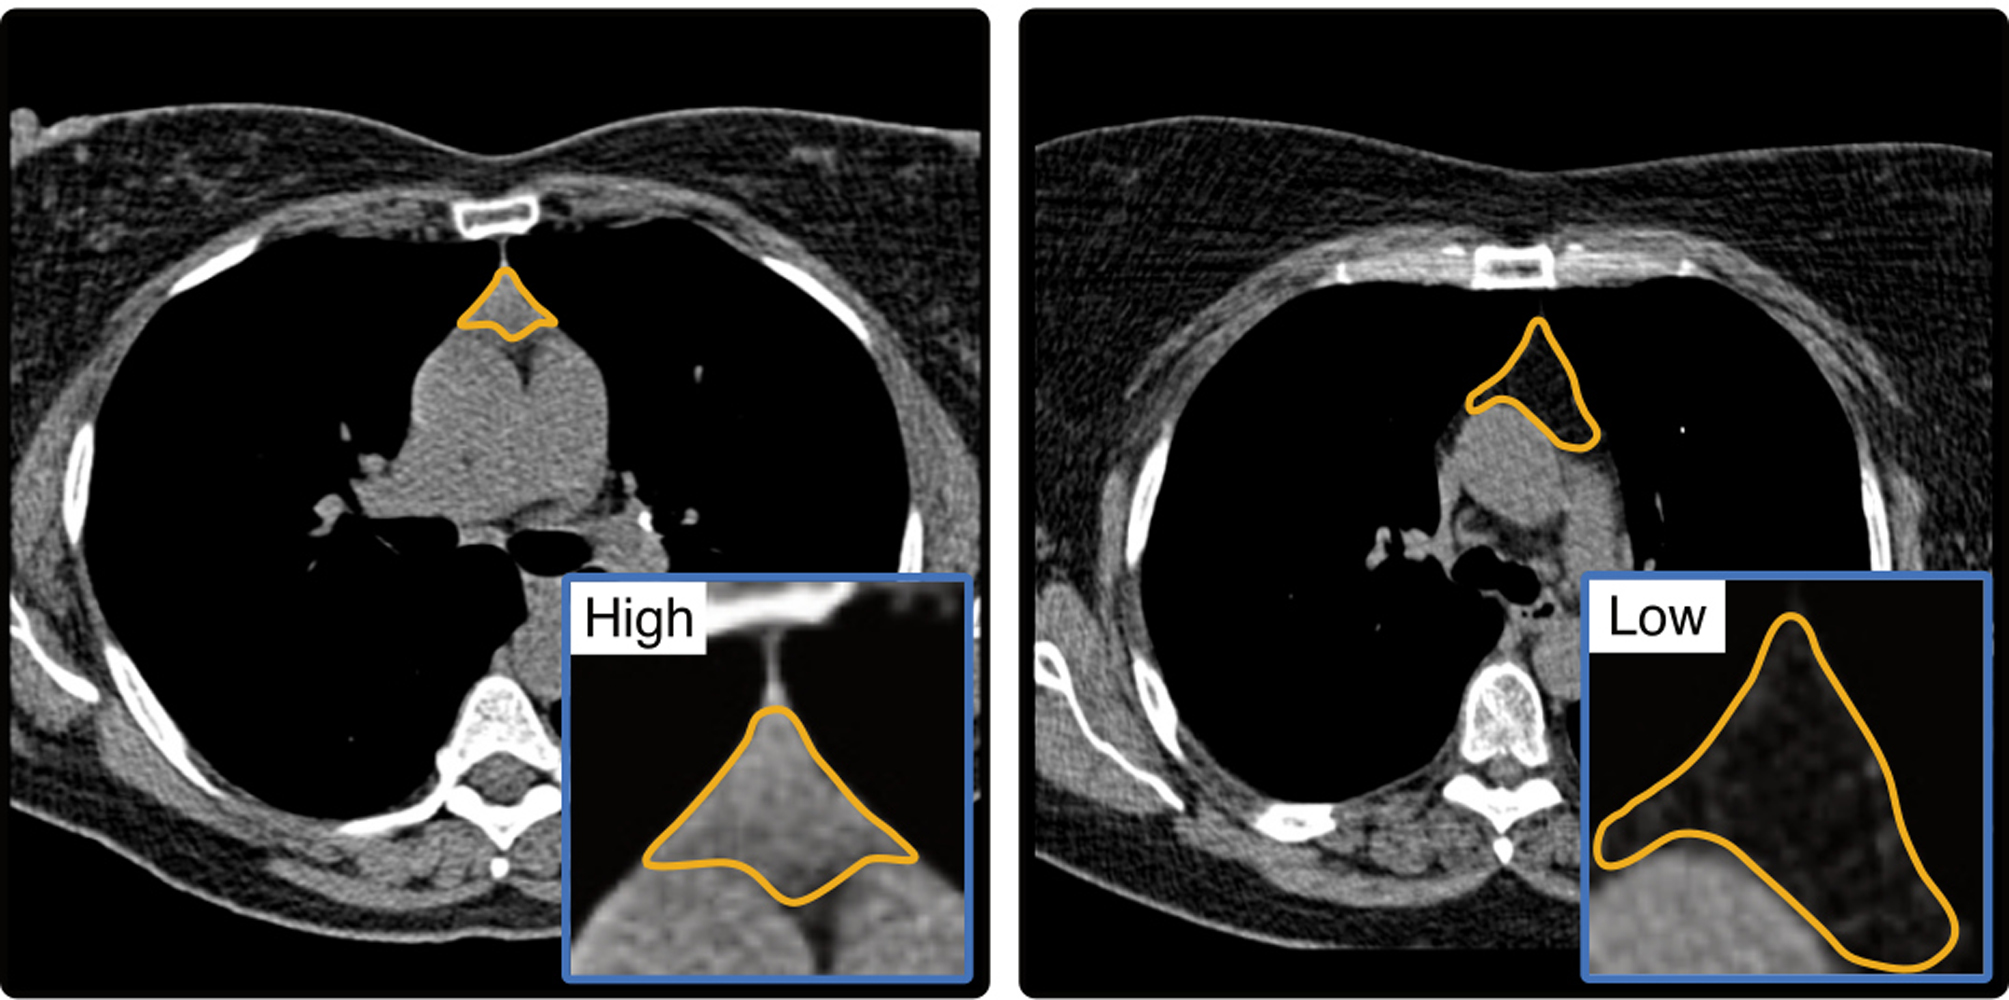

“The publications in Nature underscore the extraordinary scientific and clinical relevance of this work. They impressively demonstrate the contribution modern imaging can make in revealing previously underestimated biological connections,” says Professor Thomas Vogl, Director of the Clinic for Radiology and Nuclear Medicine at Universitätsmedizin Frankfurt. “If it becomes possible to analyze thymus health early and reliably, individual disease risks can be identified much earlier and counteracted in a targeted way – long before clinical symptoms appear.” Thymus health, as determined using routinely collected computed tomography imaging data, could therefore offer a new approach to identifying disease risks at an early stage and initiating targeted preventive measures. In imaging, thymus health can be assessed based on the degree of fatty degeneration. Lower levels of fat infiltration generally indicate better immune function.

Two international studies led by Harvard University (Boston) and research partners in Maastricht, Aarhus, London, and Frankfurt support this hypothesis. Dr. Simon Bernatz, first author of the publication, physician and research associate at the Clinic for Radiology and Nuclear Medicine at Universitätsmedizin Frankfurt, explains: “Our analyses show for the first time that thymus health seems to be an independent predictor of survival and disease risks. Particularly noteworthy is that we were able to obtain this information from routine computer tomography (CT) scans.”